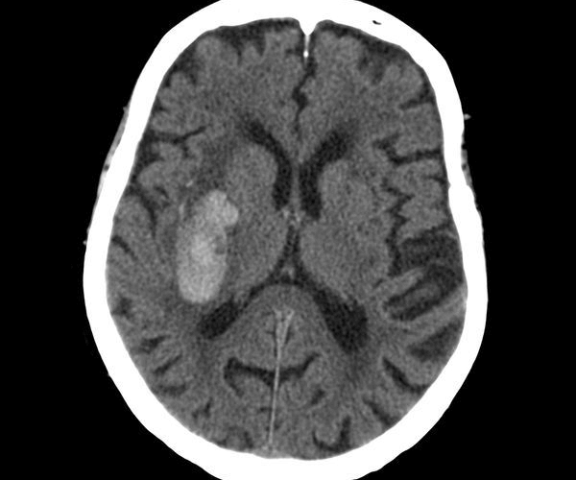

КТ головного мозку до і з внутрішньовенним підсиленням (стандартне)

Високоточне діагностичне обладнання

для уточнення діагнозу та розробки плану операці